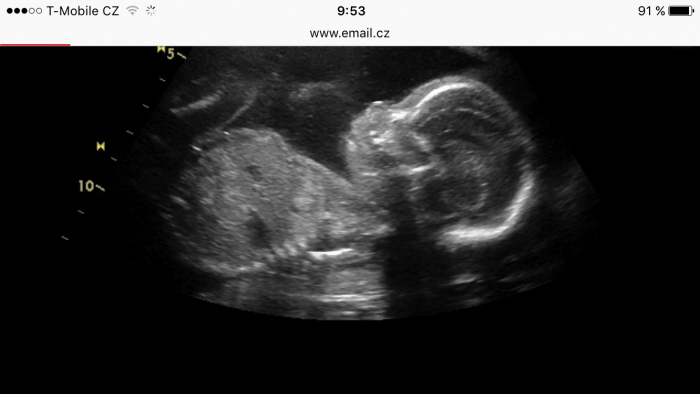

Ahoj holky, my byli dnes na kontrole, vše v poradku, pindik tam stále byl, takže snad uz se nic nezmění :) triple test dobrý, riziko 1:50 000 :-) jen se nechtěl ukazovat, byl hlavou dolu a obličejem do břicha, tak do nej dr. musela zduchnout, aby se otočil, asi jsme ho vyrusili ze spánku :)) uz jsme objednany na test na tehu cukrovku, pry to je tak na 3 hodky, asi umru hlady :-D Plánujete 3D ci 4D utz? Objednávaly jste se na nej nejak dopředu? Dávám sem tu moji malou opicku, 360g pry muze mit tak 25cm, dle utz o malinko starší, nez je to možné, v tom Gennetu to nejak divne měří :-D Pekny vikend všem!